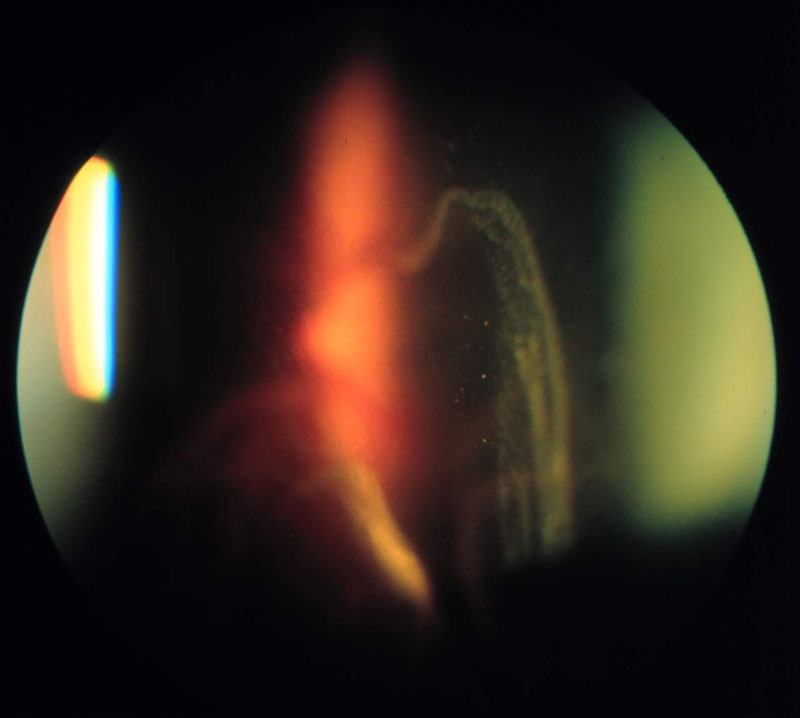

2. ábra

2. ábra Vitrectomia, siliconolaj beültetés után alul bullosus jellegű retina leválás alakult ki. A TransEquator lencsével készített felvételen a látószög az előbbinél kisebb, a kép felbontása azonban nagyobb.